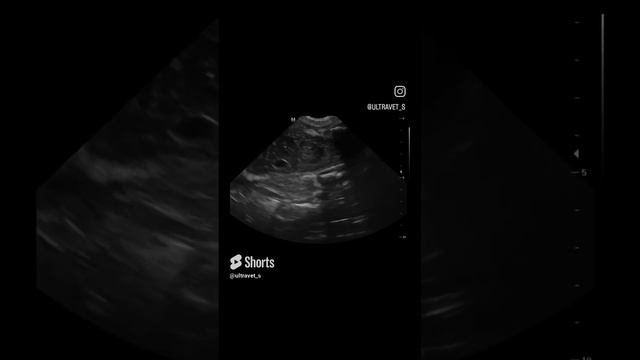

Узи собаке нижний

Узи собаке нижний 106 фотографий